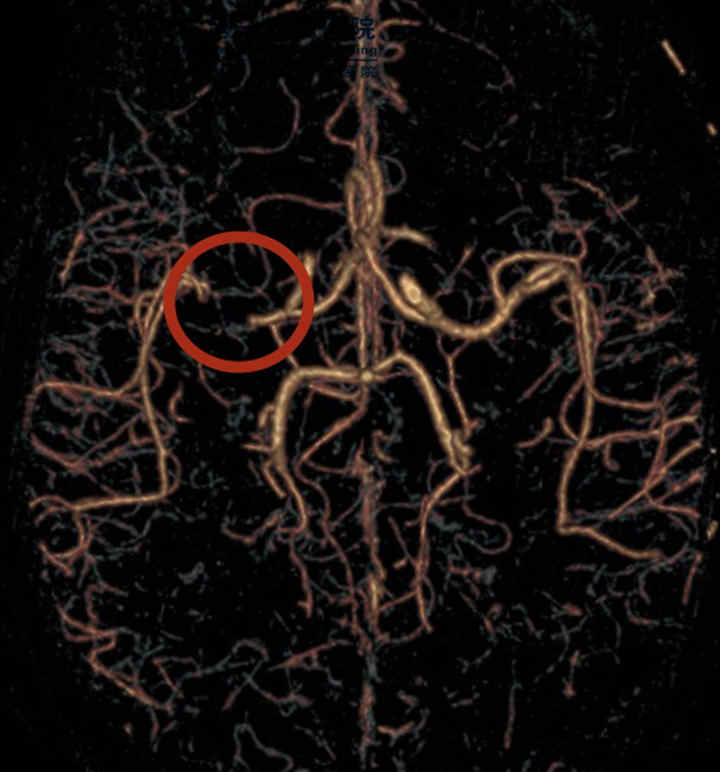

CTA提示右侧大脑中动脉重度狭窄(红色圆圈所示)

患者右侧大脑中动脉闭塞,可出现大面积脑梗死,严重可出现脑疝,进一步危及生命,经卒中团队讨论后,患者有急诊介入治疗指征,与患者家属充分沟通后,立即予行急诊取栓治疗。

大脑中动脉重新开通